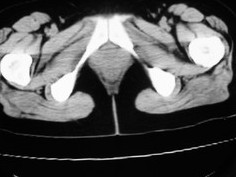

女42岁肛门下坠感4月余.

肛周脓肿临床症状比较典型,此患者:女42岁肛门下坠感4月余,与其不符

考虑:子宫直肠窝少量积液(盆腔炎所致)。

子宫轻度右倾,体后方见小似新月形低密度区,道格拉斯窝周围间隙欠清晰,有索条模糊影阴,多考虑:肛周慢性感染可能。